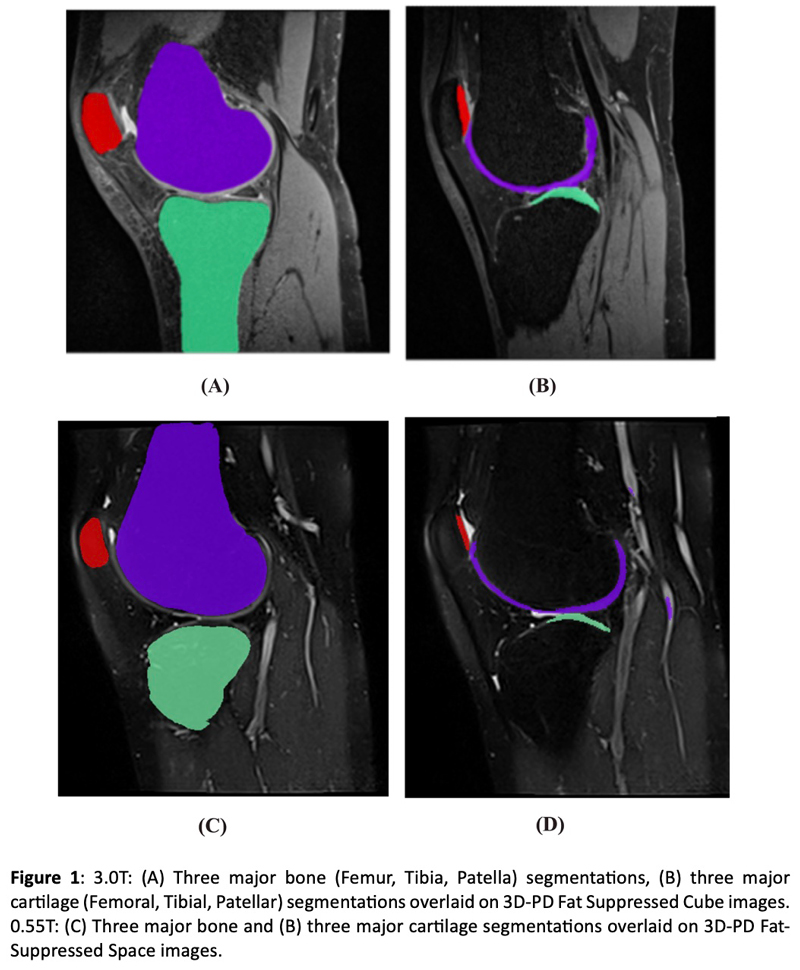

Figure 1: 3.0T (A) Three major bone (Femur, Tibia, Patella) segmentations, (B) three major cartilage (Femoral, Tibial, Patellar) segmentations overlaid on 3D-PD Fat Suppressed Cube images. 0.55T: (C) Three major bone and (B) three major cartilage segmentations overlaid on 3D-PD Fat-Suppressed Space images.